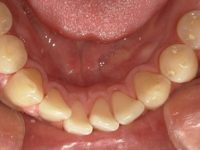

ANBIシドニーでは、ほとんどの治療にマイクロスコープを活用。

肉眼では見えない歯石や汚れをしっかり捉え、

歯茎に優しい

痛みが極めて少ない

効果が長持ち

という、ワンランク上のクリーニングを可能にしています。

これは一般的なクリニックではまだ珍しい“高度機器”。

せっかくシドニーでケアするなら、“精密ケア”できれいに、そして長く健康に。